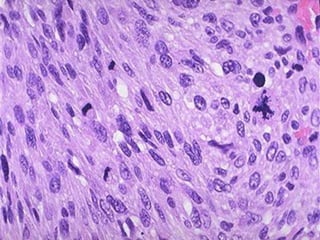

Carcinoma verrucoso

 Variante de carcinoma

epidermoide (5%)

 Mucosa bucal, encía

 Lesión irregular, indurada,

exofítica de superficie

blanquecina o grisácea

 Epitelio acantótico de

bordes “empujantes”

 Histológicamente con

ausencia de atipia

 Rp. quirúrgico. Proscrita

RT

Carcinoma verrucoso de lengua

Carcinoma verrucoso  Variantede carcinoma epidermoide (5%)  Mucosa bucal, encía  Lesión irregular, indurada, exofítica de superficie blanquecina o grisácea  Epitelio acantótico de bordes “empujantes”  Histológicamente con ausencia de atipia  Rp. quirúrgico. Proscrita RT